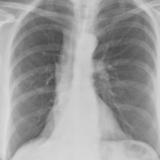

RLL Collapse 1 PA

Date: 02/28/2004

Views: 3496